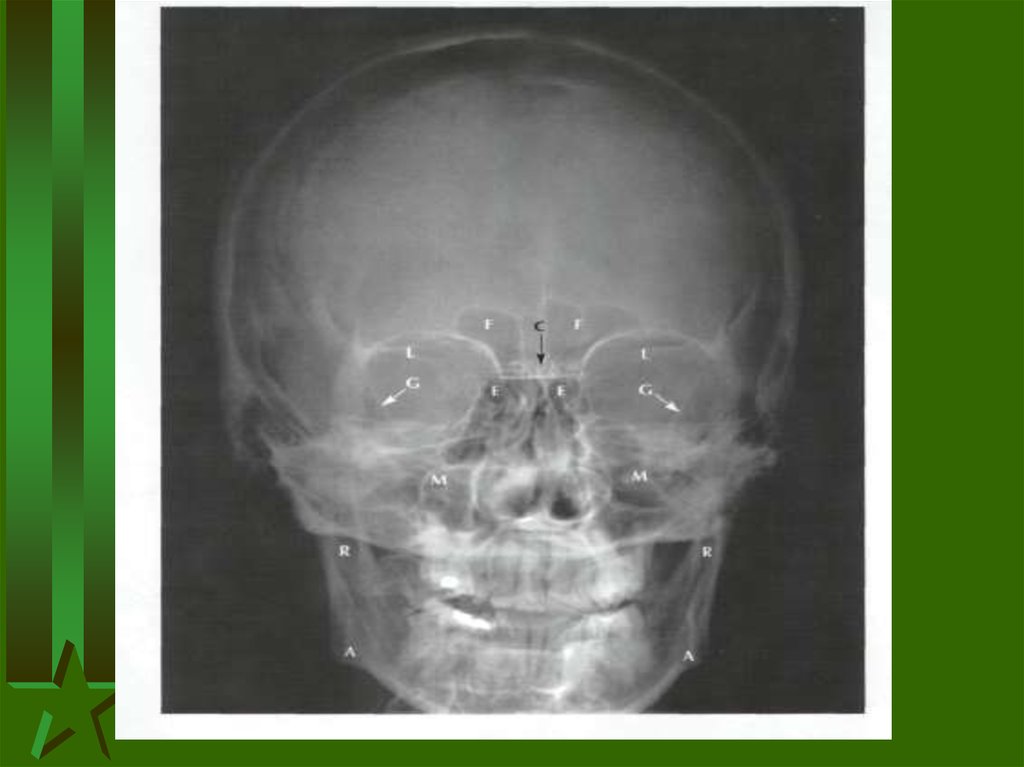

Загальна остеологія